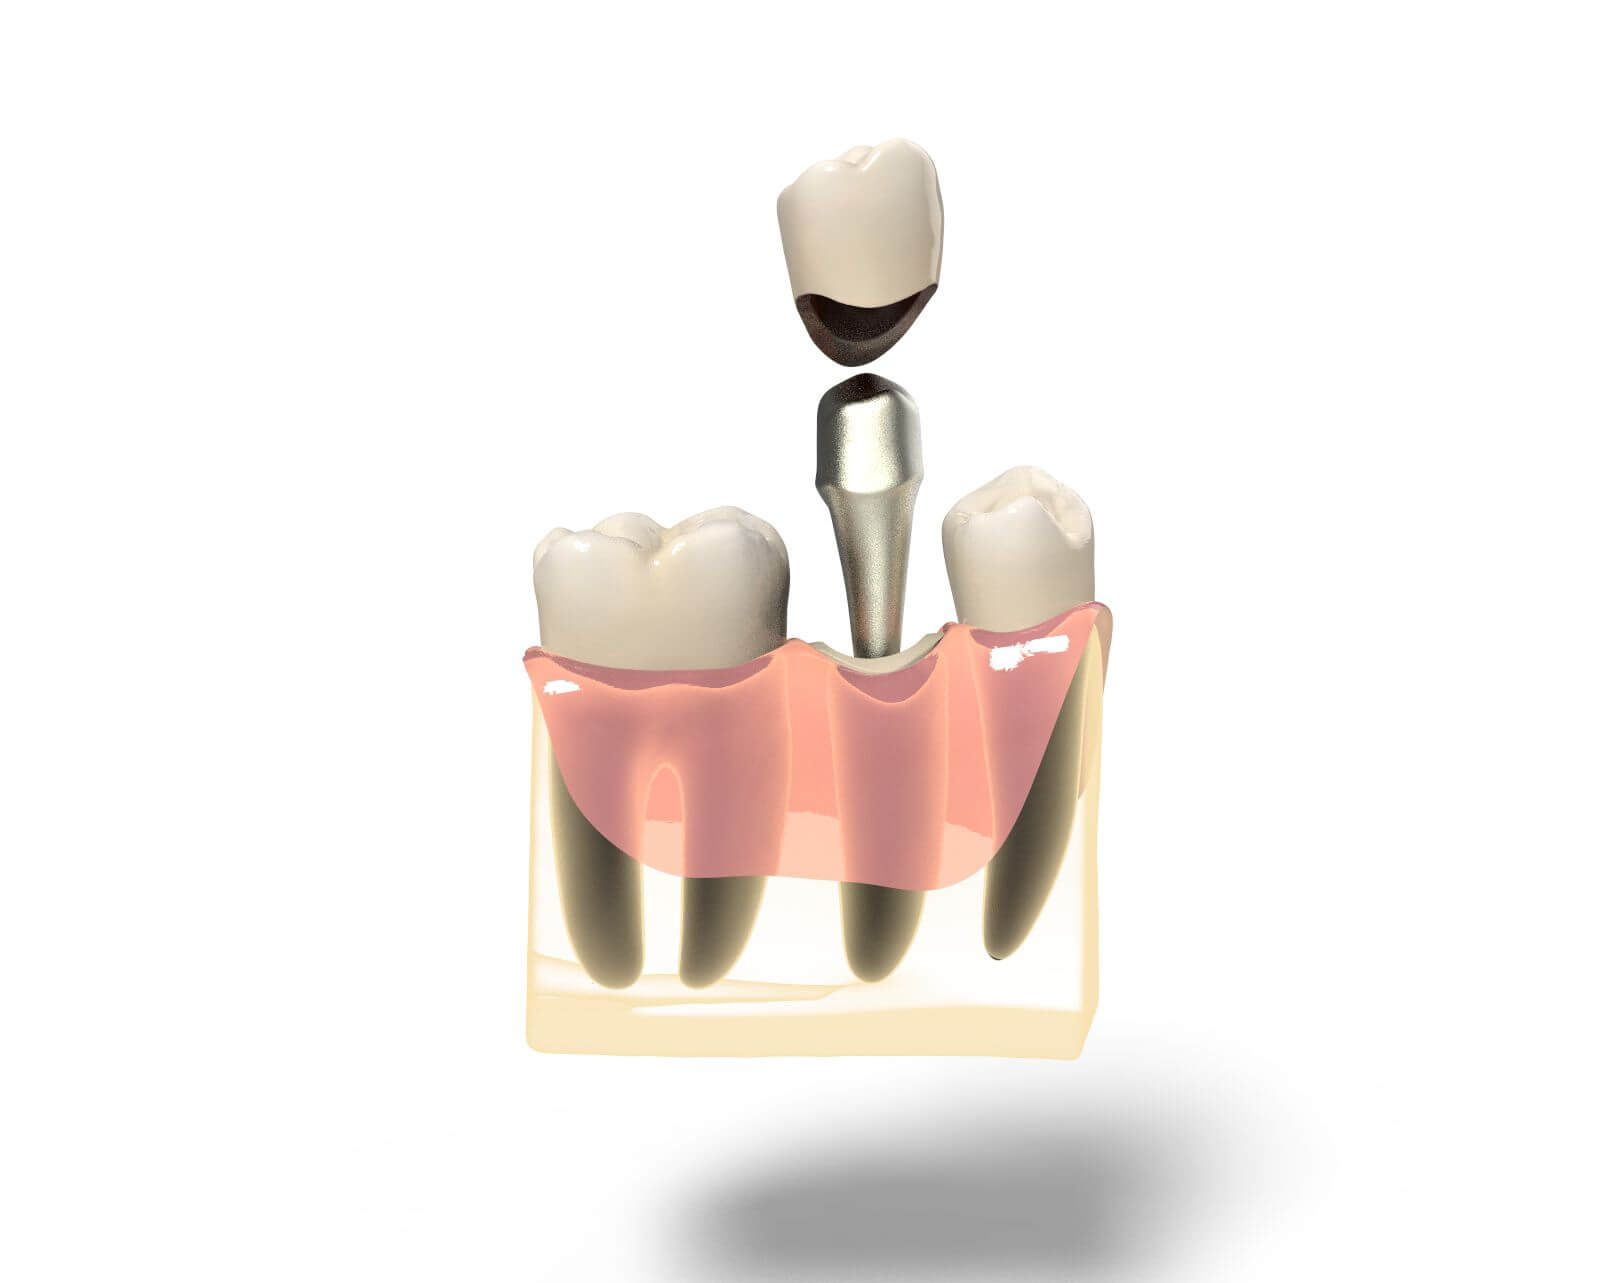

Культя зуба это

Культя зуба это 106 фото